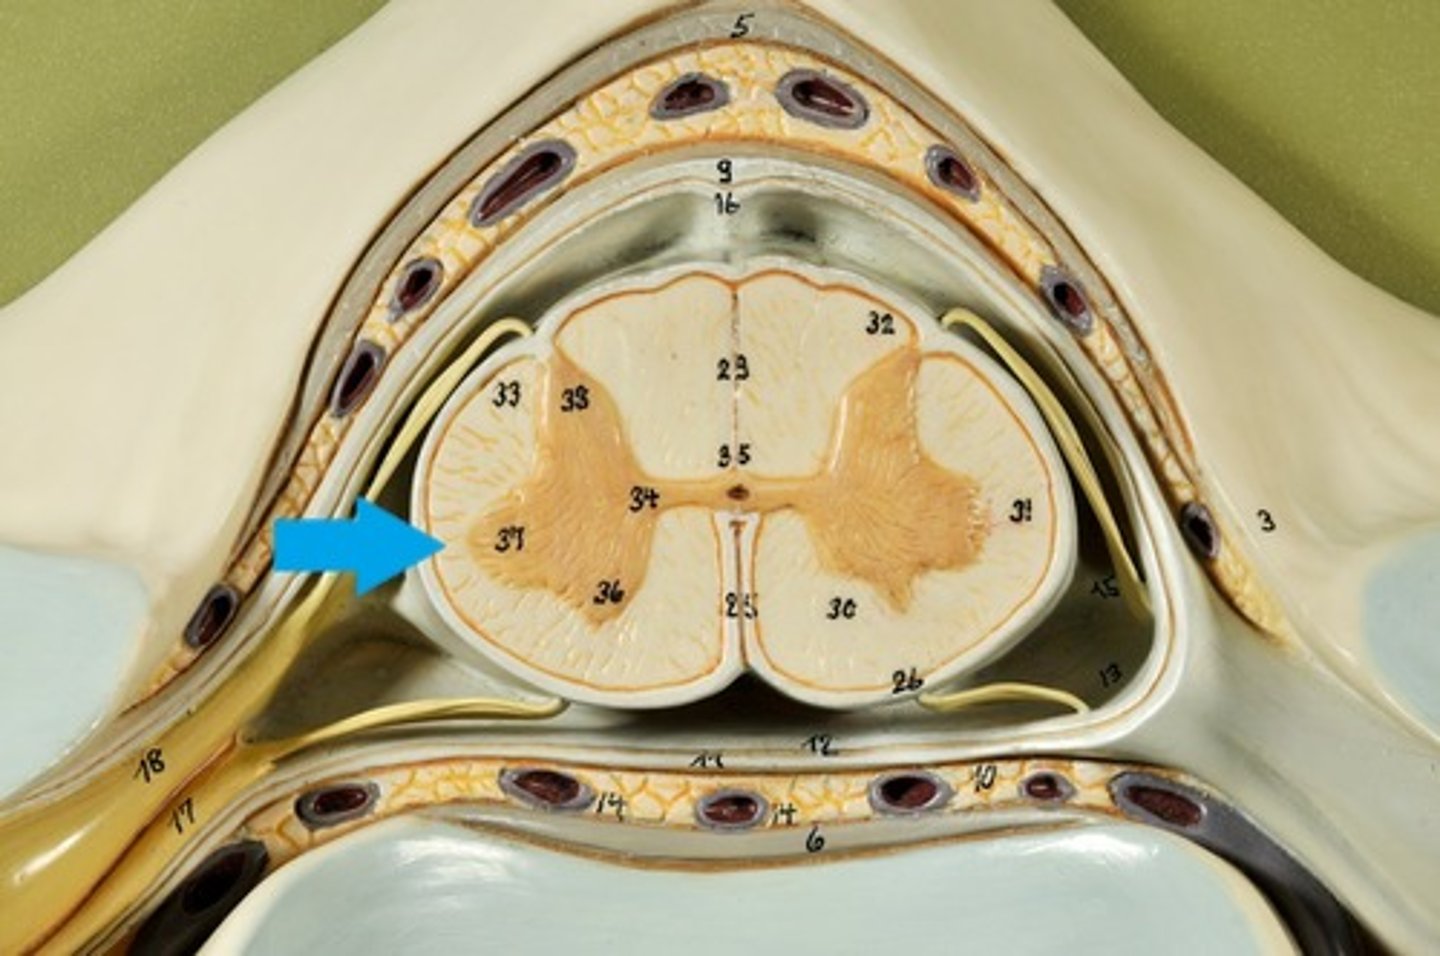

Spinal cord Anatomy (cross-sectional)

1)Internal butterfly shaped gray matter,

2)Exterior white matter,

3)Central canal filled with cerebrospinal fluid (CSF),

4)Cushioned & protected by meninges,

5)Pia mater,

6)Spinal nerves leave at the level of each vertenrae

Horns of Spinal Cord Anatomy

Dorsal Horns,

Ventral Horns,

Lateral Horns

Dorsal Horns

Lateral Horns

Ventral Horns

Interneurons

exterior white matter of the spinal cord

Ascending (sensory) and descending (motor) myelinated nerve tracts,

Posterior, anterior, lateral columns or funiculi

Posterior Columns

Anterior Columns

Lateral Columns/ funiculi

Central canal filled with what?

Central canal filled with cerebrospinal fluid (CSF)

Cushioned and protected by meninges

1) Cover the spinal cord

2) Dura mater, Arachnoid & Pia mater

dura mater of spinal cord

1) Separated from the periosteum by the epidermal space (fat, blood vessels)

2) Subdural space between dura and arachnoid mater

Dura Mater